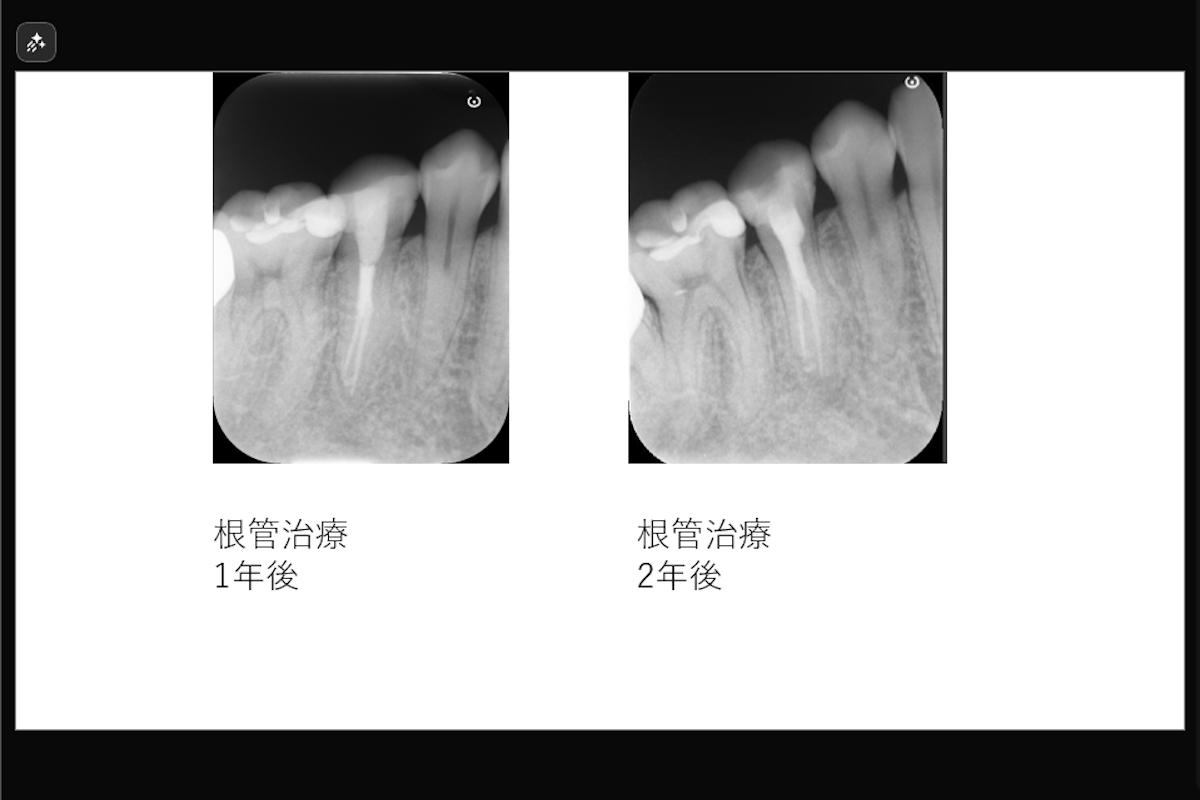

【根尖部外部吸収を伴う2根管性下顎第二小臼歯の症例】「近医で根管治療するも咬むと痛い。」

「近医で根管治療するも咬むと痛い。」ということで来院された患者様の症例です。

• 根尖部外部吸収を伴う2根管性下顎第二小臼歯の症例

• 治療内容: 下顎右側第二小臼歯 根管治療(レーザーを用いた根管洗浄、MTAを用いた根管充填)

• 治療のリスク: 残存歯質の厚みによって歯根破折のリスク、経過によっては外科的歯内療法